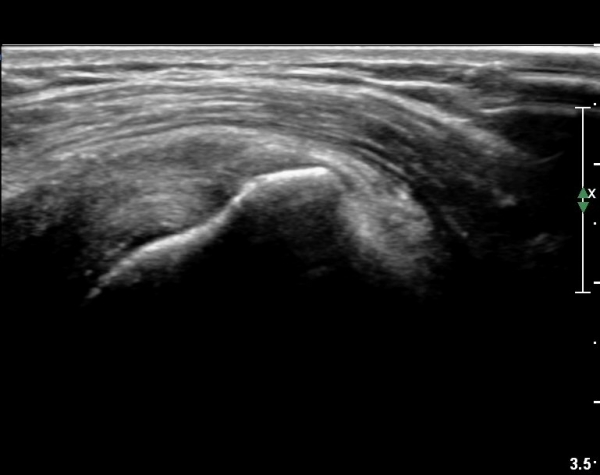

ȸÀü±Ù°³°£°Ý(rotator cuff interval) Ⱦ´Ü¸é°Ë»ç¿¡¼­ Á¡¾×³¶ÀÇ ºÎÁ¾ÀÌ °üÂûµÈ´Ù(»çÁø 3).